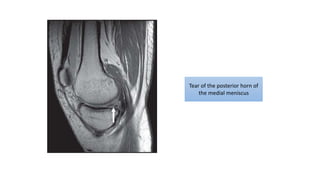

Tear of the posterior horn of

the medial meniscus

Tear of theposterior horn of the medial meniscus